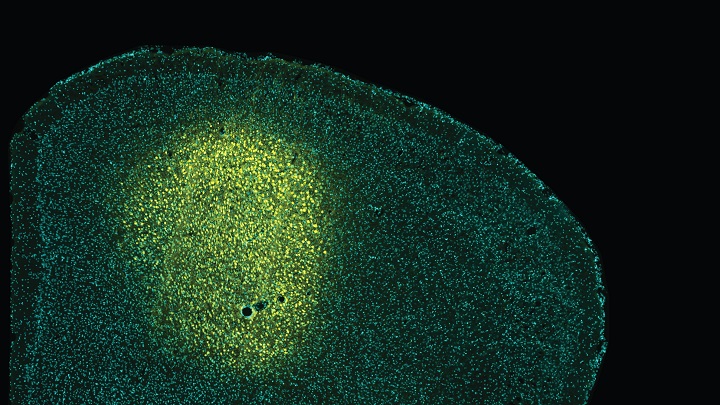

La administración de sensores fluorescentes en la corteza M2 (en amarillo) ha permitido entender cómo la actividad aberrante de esta corteza está relacionada con alteraciones en la integración de estímulos visuales.

En los pacientes, el área cerebral más afectada desde el inicio de la enfermedad es la corteza premotora —la corteza M2 en ratones— que participa en las funciones cognitivas y los procesos de percepción. En el caso de los modelos animales, la M2 se relaciona con déficits en el aprendizaje motor. Además, también se sabe que esta área cortical es capaz de proyectar los axones neuronales hacia diversas regiones del cerebro más allá del núcleo estriado.

Ahora, el nuevo trabajo identifica por primera vez que la corteza M2 envía diferentes proyecciones axonales hacia otra estructura anatómica del cerebro —el colículo superior (SC)—, que están profundamente deterioradas y podrían relacionarse con la sintomatología de la enfermedad.

En el marco del trabajo, la técnica de resonancia magnética funcional reveló la reducción de la conectividad funcional entre la corteza M2 izquierda y todas las regiones cerebrales analizadas en ratones modelos de la enfermedad. Mediante la aplicación de otras metodologías innovadoras para controlar y modular la actividad neuronal —ontogenética, electrofisiología, fotometría y quimiogenética— el equipo descubrió que la falta de actividad de la corteza M2 podría ser responsable de las respuestas alteradas en los modelos de Huntington.